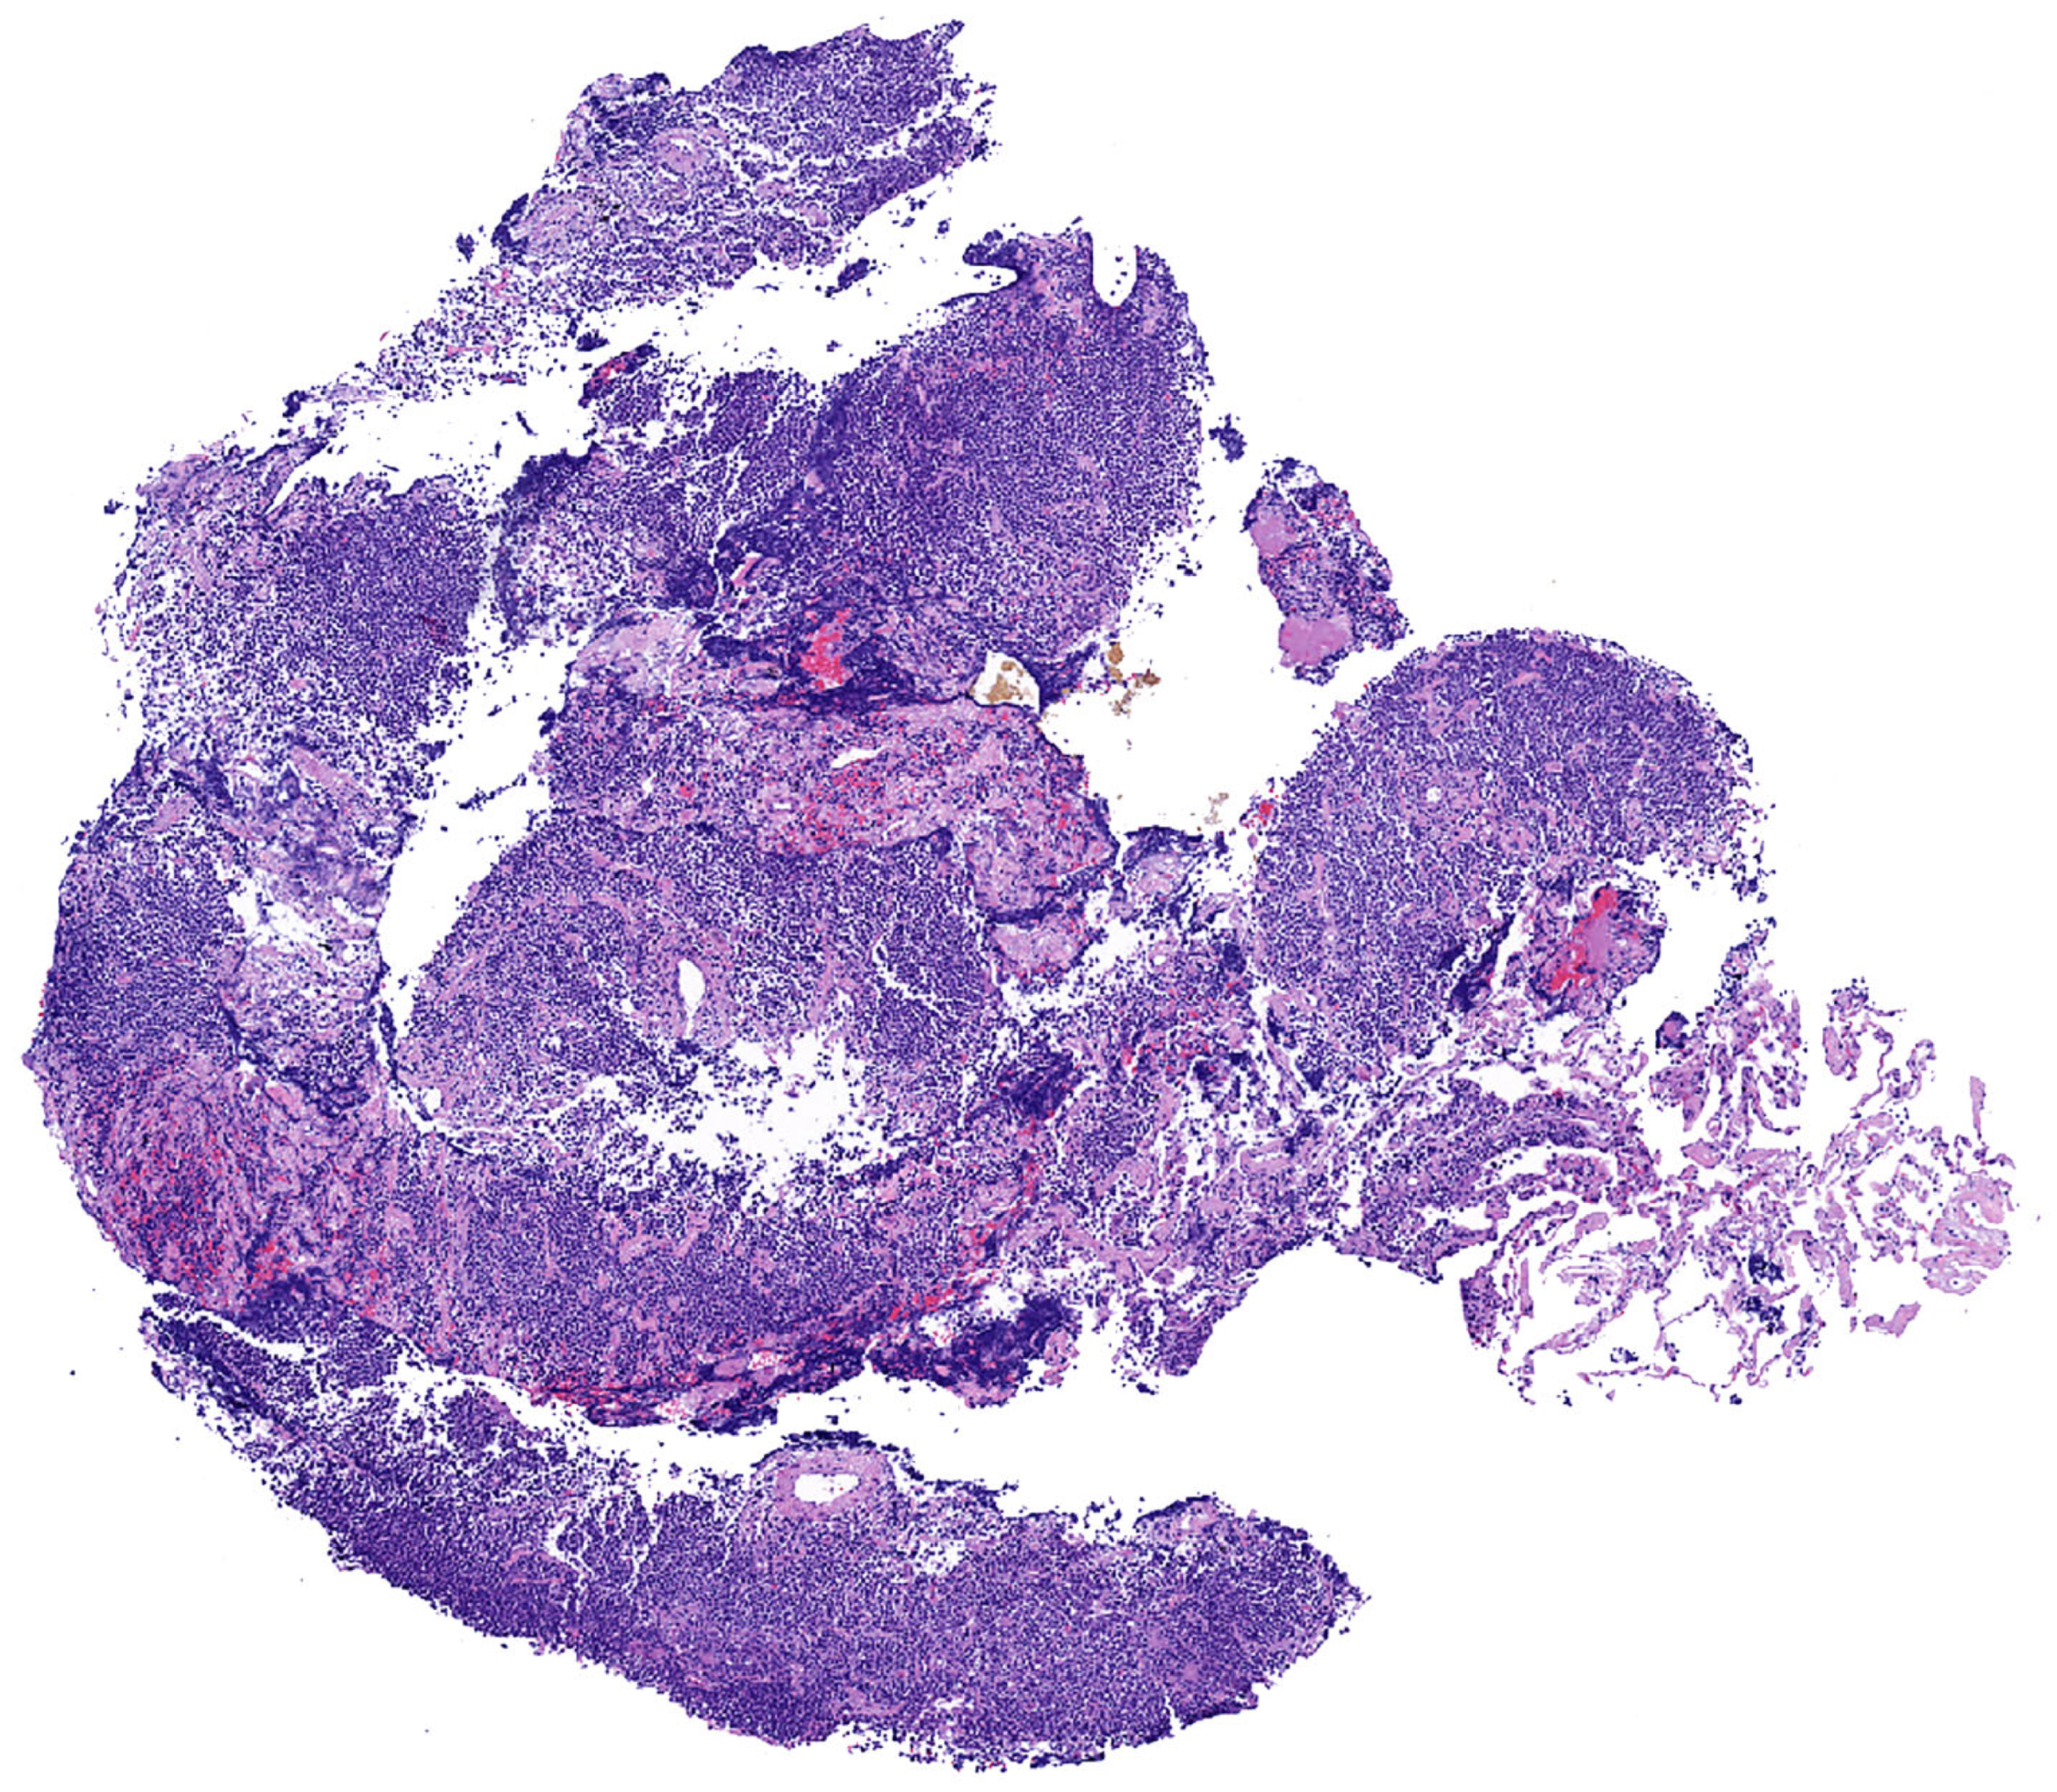

Histopathologic features in biopsies. MALT lymphoma is a polymorphic lymphoma composed predominantly of sheets of small lymphocytes, centrocyte-like cells, and monocytoid cells, with few scattered large immunoblast-like cells and a variable number of plasma cells. This process typically effaces the lung parenchyma (Figure 2 and Figure 3).

Figure 2.

Pulmonary MALT lymphoma; core biopsy. There is effacement of the lung architecture by small cell lymphoma with associated areas of fibrosis.

Importantly, the edges of a pulmonary MALT lymphoma are ill-defined and show alveolar septal expansion with numerous lymphocytes with variable degrees of alveolar edema, intra-alveolar proteinaceous debris, and reactive pneumocyte changes (Figure 8).

Figure 8.

(A) Edge of a pulmonary MALT lymphoma. If a core needle biopsy passes through the delineated area, the morphologic features will be indistinguishable from (B) lymphoid interstitial pneumonia (LIP). Imaging correlation is mandatory in this case since MALT lymphoma usually presents as a mass, whereas LIP presents as ground glass opacities. (C) In contrast to MALT lymphoma, the edge of nodular lymphoid hyperplasia is sharply demarcated from the lung parenchyma.

These features are morphologically indistinguishable from LIP (Figure 8). Therefore, mandatory correlation with imaging is needed in a transbronchial or core needle biopsy with morphologic features of LIP where the imaging shows a mass rather than diffuse ground-glass opacities. In this setting, CD3 and CD20 IHC should be performed to document the type of predominant lymphocytes (LIP usually has more CD3+ than CD20+ cells, whereas MALT lymphoma is the opposite). We recommend signing cases of nodules or masses with morphologic features of LIP in a biopsy as ”prominent septal alveolar lymphocytic infiltrate, B-cell-rich or T-cell-rich” (based on the IHC results) and comment that the possibility of MALT lymphoma cannot be entirely excluded, particularly if the lymphoid infiltrate is B-cell-rich. Close clinical and imaging correlation as well as a recommendation for additional material with a sample submitted for flow cytometry are encouraged. Lastly, the edges of nodular lymphoid hyperplasia are typically sharply demarcated from the lung (Figure 8) in contrast to the findings described for LIP and MALT lymphoma, but this is difficult to appreciate in a core biopsy.